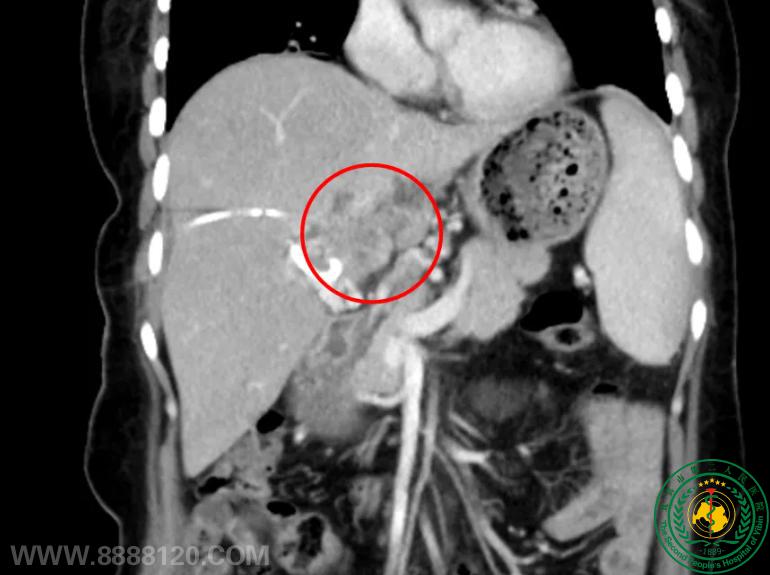

突破生命禁区!我院介入科成功完成川南首例、四川地市级医院首例经皮肝肿瘤纳米刀消融术,为肝门部恶性肿瘤患者带来新希望

突破生命禁区!我院介入科成功完成川南首例、四川地市级医院首例经皮肝肿瘤纳米刀消融术,为肝门部恶性肿瘤患者带来新希望62545